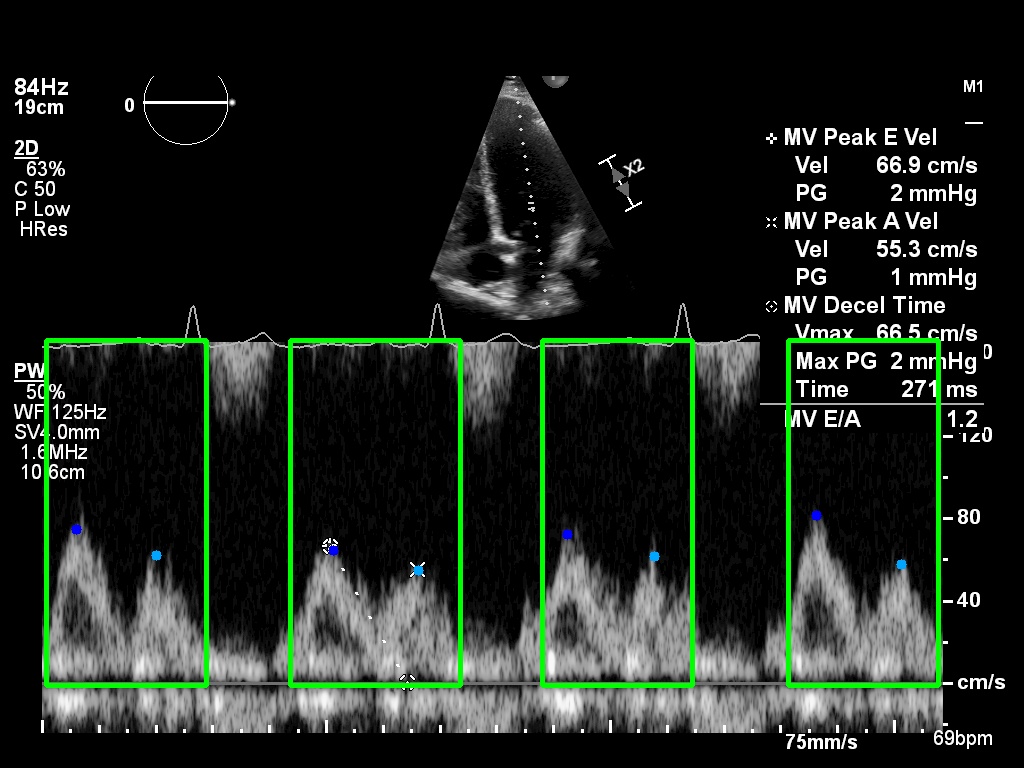

The UNITY MInD dataset provides Doppler echocardiography images of mitral inflow, a key measure for evaluating diastolic function.

Transmitral Doppler traces capture two main phases of ventricular filling:

Sample Doppler inflow image with annotated E- and A-wave peaks.